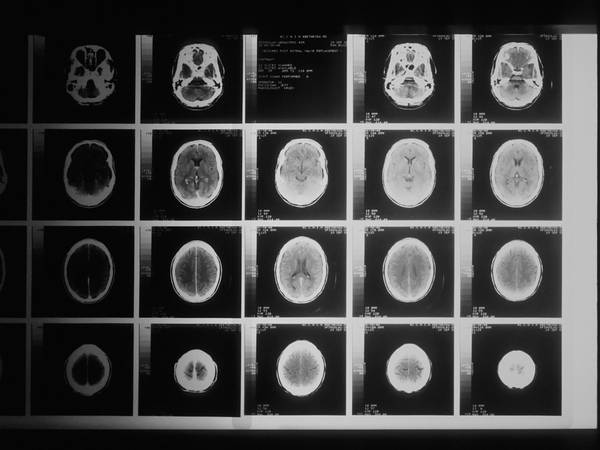

برخلاف مطالعات اپیدمیولوژیک قبلی، او به کالبدشکافی مغز بیماران در مرکز تحقیقاتی بیماری آلزایمر دانشگاه پرداخت.

او گفت: «ما رابطه نسبتا پایدار و ثابتی بین داشتن سابقه سرطان و سطوح پایینتر آسیبهای آمیلوئید در مغز پیدا کردیم که نشانه مشخص بیماری آلزایمر است.»